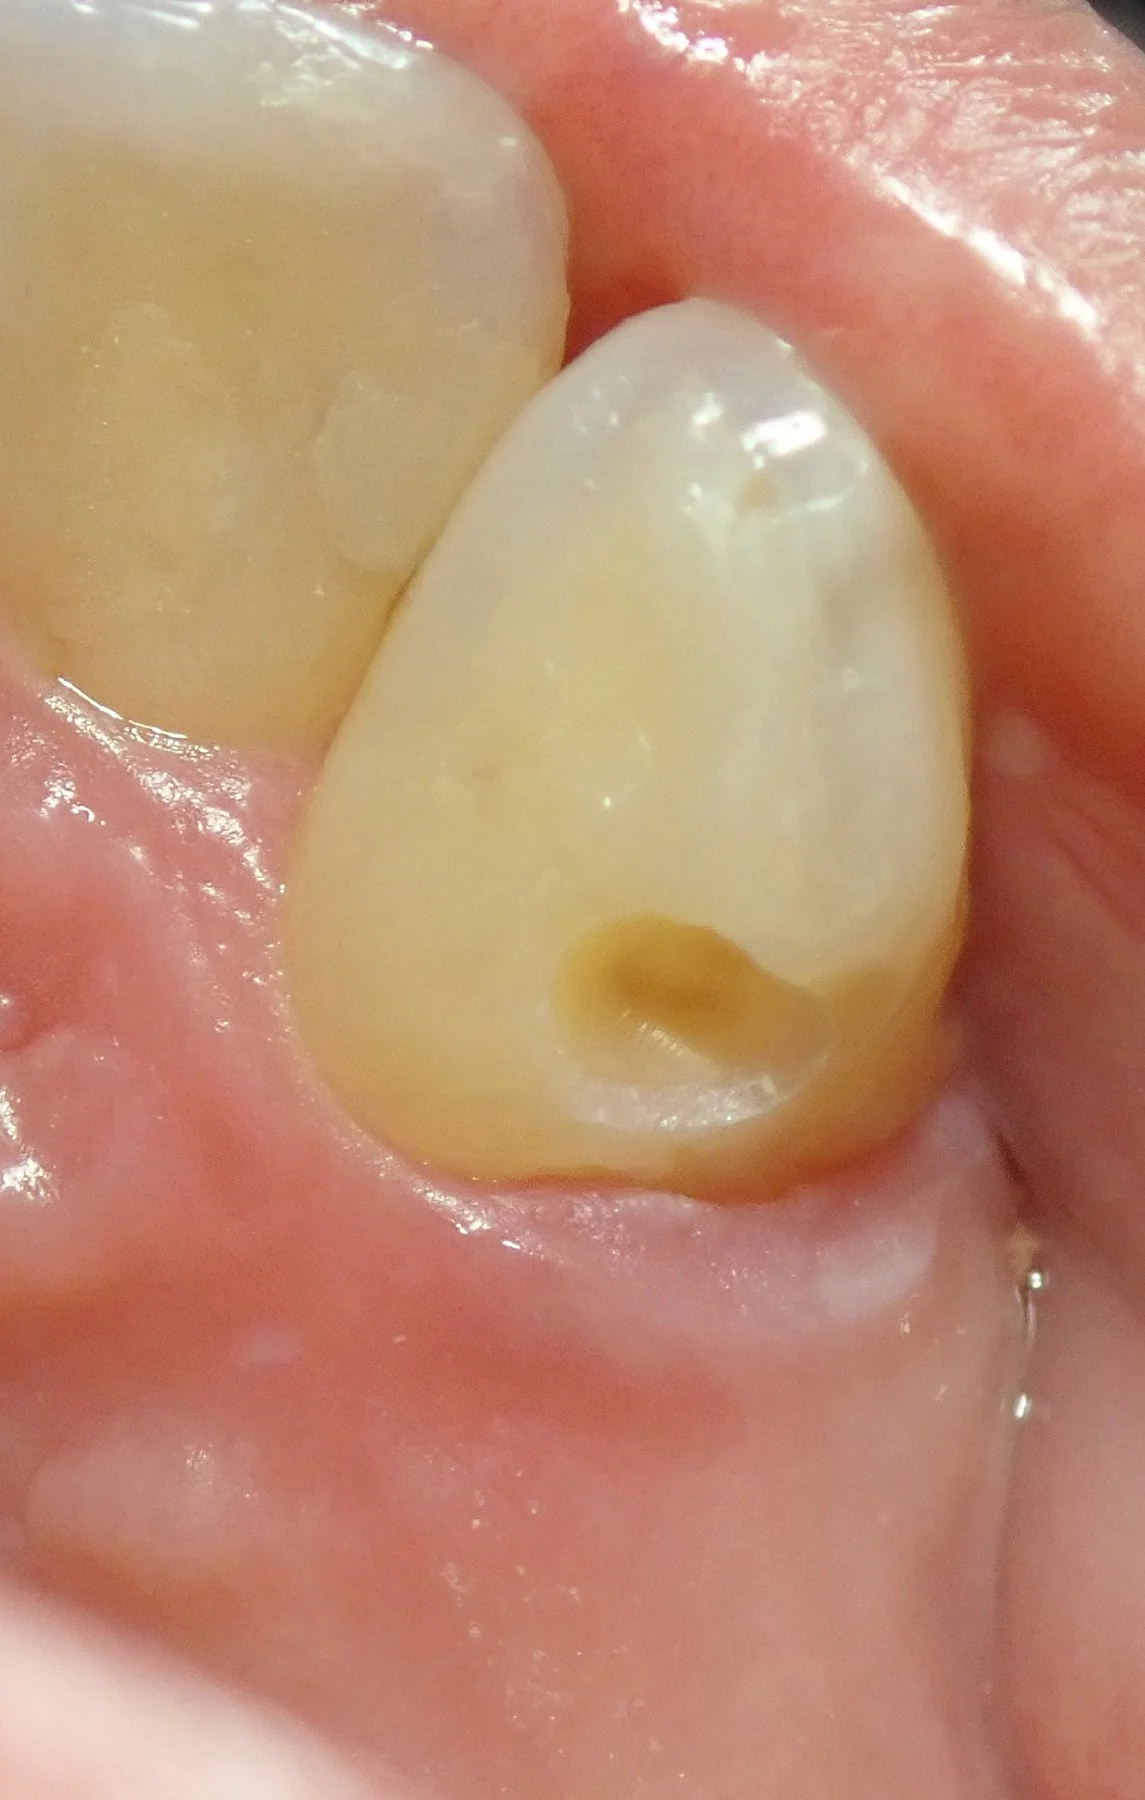

そういう時に、

こんな感じで、虫歯を取る前にシリコン素材のかみ合わせを取る材料で元の形をインキしておくと非常に楽に本来の形態通りに詰められるのでお勧めです。

固まったものを歯から外すとこうなります。